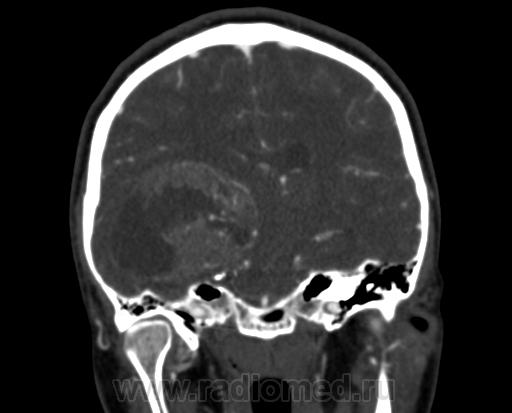

Молодая женщина, 29 лет. Обратилась на прием к неврологу 26.10.12г с  болями в шее, назначено лечение амбулаторно по сосудистой головной боли, остеохондрозу.. После 14.11.12г обратилась к другому неврологу повторно, 16.11.12г направлена в стационар. Жалобы: на снижение зрения, головные боли, головокружения, слабость, повышение температуры. Провели СКТ головного мозга натив и контрастирование. Подскажите пожалуйста, коллеги- Это опухоль? тогда какая (глиобластома, невринома, менингиома?) и локализацию. Спасибо.

Сканы с контрастированием.

Нативное исследование.

Одно можно сказать точно: это не менингиома и не невринома (у тех структура однородная). Это Вам в помощь http://www.radiologyassistant.nl/en/p47f86aa182b3a/brain-tumor-systematic-approach.html

Мне кажется, что тут субэпендимарная глиома. Указываете степень дислокации, накопления и к нейрохирургам.

Согласна с Андреем Юрьевичем. Все остальное возможно, в том числе олигодендроглиома. Впрочем не принципиально. К нейрохирургам!

Только что узнала результаты вскрытия.Гистология пока не готова.

Глиобластома с прорастанием стенки правого бокового желудочка, выраженный отек, смещение срединных структур, вклинение миндалин мозжечка в БЗО.